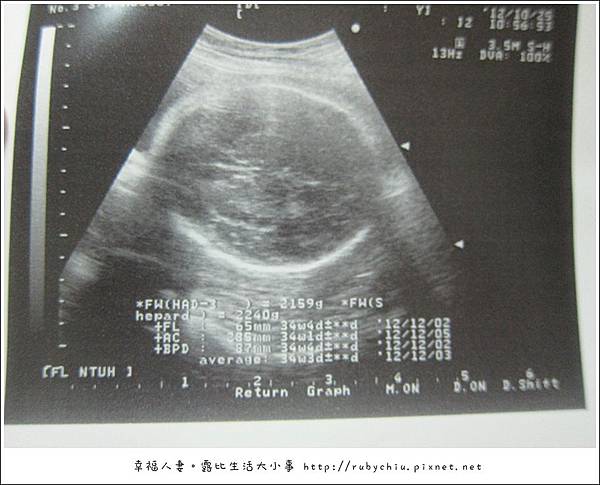

33週了!上面這張超音波非常確定是"紀念品"大頭啦! ^^

沒有妊娠糖尿病...嘿嘿!接著就拍超音波啦!

醫生第一句話是!"很大一隻喔" 唉唷~ 怎麼可以說妹妹很大一隻~ 真是~

接著就量頭圍,肚圍,腿骨,心跳~ 都很正常,小朋友比預定週數大了一週...

體重2200!!! 跟上次比大了500公克! 所以有1.3公斤是胖在媽媽身上~